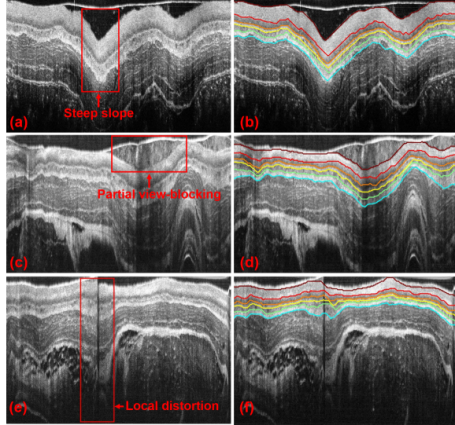

研究通过应用基于L1-L0的图像去噪与平滑高分辨率成像处理技术、图论及最短路径搜索优化技术等进行活体组织层析图像的自动分割与分析,突破微米级活体组织结构的分析和信息提取。并在此基础上,开展了活体组织的光学着色研究,模拟显微成像原理对组织分层着色,凸显组织内部细胞元及结构,实现组织的定量分析。

特殊成像条件下的图像分析与组织的分层提取